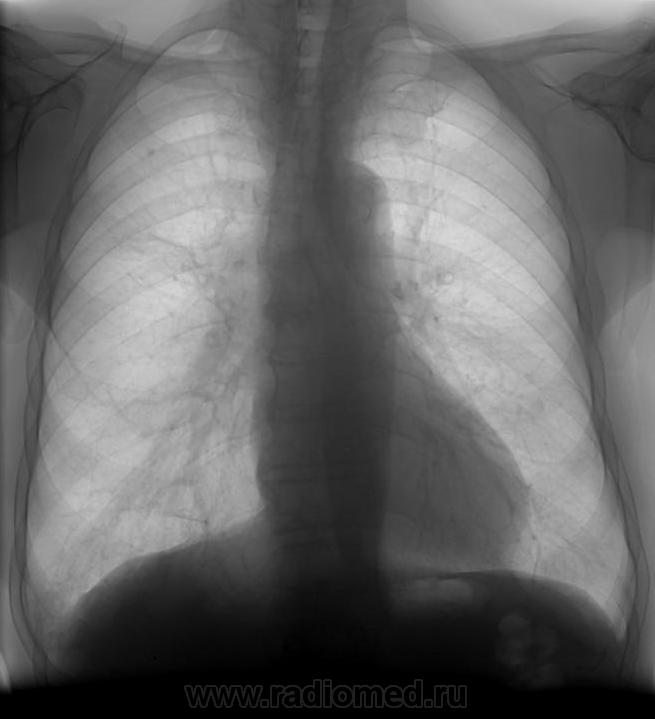

Мужчина с жалобами на кашель с вязкой мокротой, подъем температуры около недели (сколько в карте написано не было). Терапевт аускультативно слышит ослабленное дыхание в нижних отделах справа, сухие хрипы.Я хочу поставить сегментарную пневмонию в S9 справа, реактивный правый корень, но есть сомнения все ли так просто...смущает сгущение легочного рисунка во 2 межреберье справа...и что-то над левой половиной купола диафрагмы, или мне кажется? Помогите, что не вижу...

Мне кажется спокойно писать н. долевую пневмонию справа, а на контрольном снимке уточните.

Картина вполне соответствует пневмонии базальных сегментов нижней доли правого лёгкого.

и я бы поставил в S9 (+S10) справа. Подмигиваю В остальном - спокойно!

Пока "рабочее" заключение-пневмония в вышеуказанном 9 сегменте, потом контроль.

При контроле, присмотритесь к головке правого корня, да и вообще к верхней доле, на которую Вы и так обратили внимание. Если есть возможность, сделайте томографию. Так центральный рак верхней доли может проявляться.